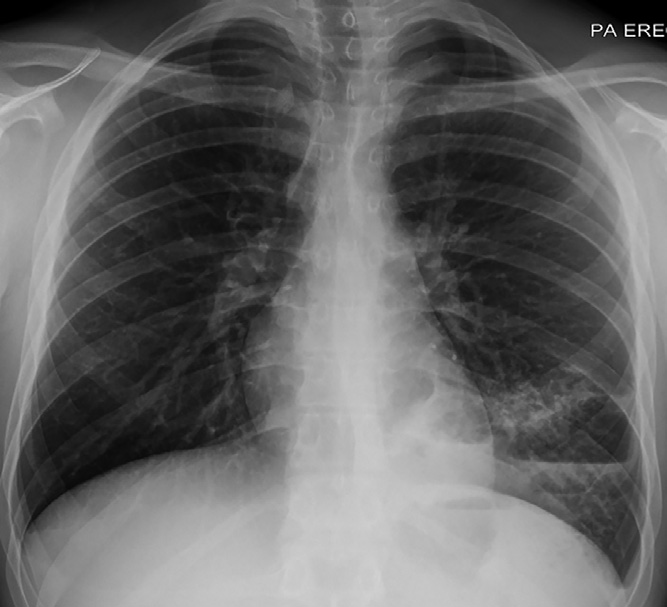

· 對于慢性射血分數降低的心力衰竭患者,如果有慢阻肺的危險因素(例如:吸煙等),或者患者有肺過度充氣的表現(例如:胸片發現肺容量和透亮度增加等),應該及時進行肺功能檢查,有助于識別慢阻肺。